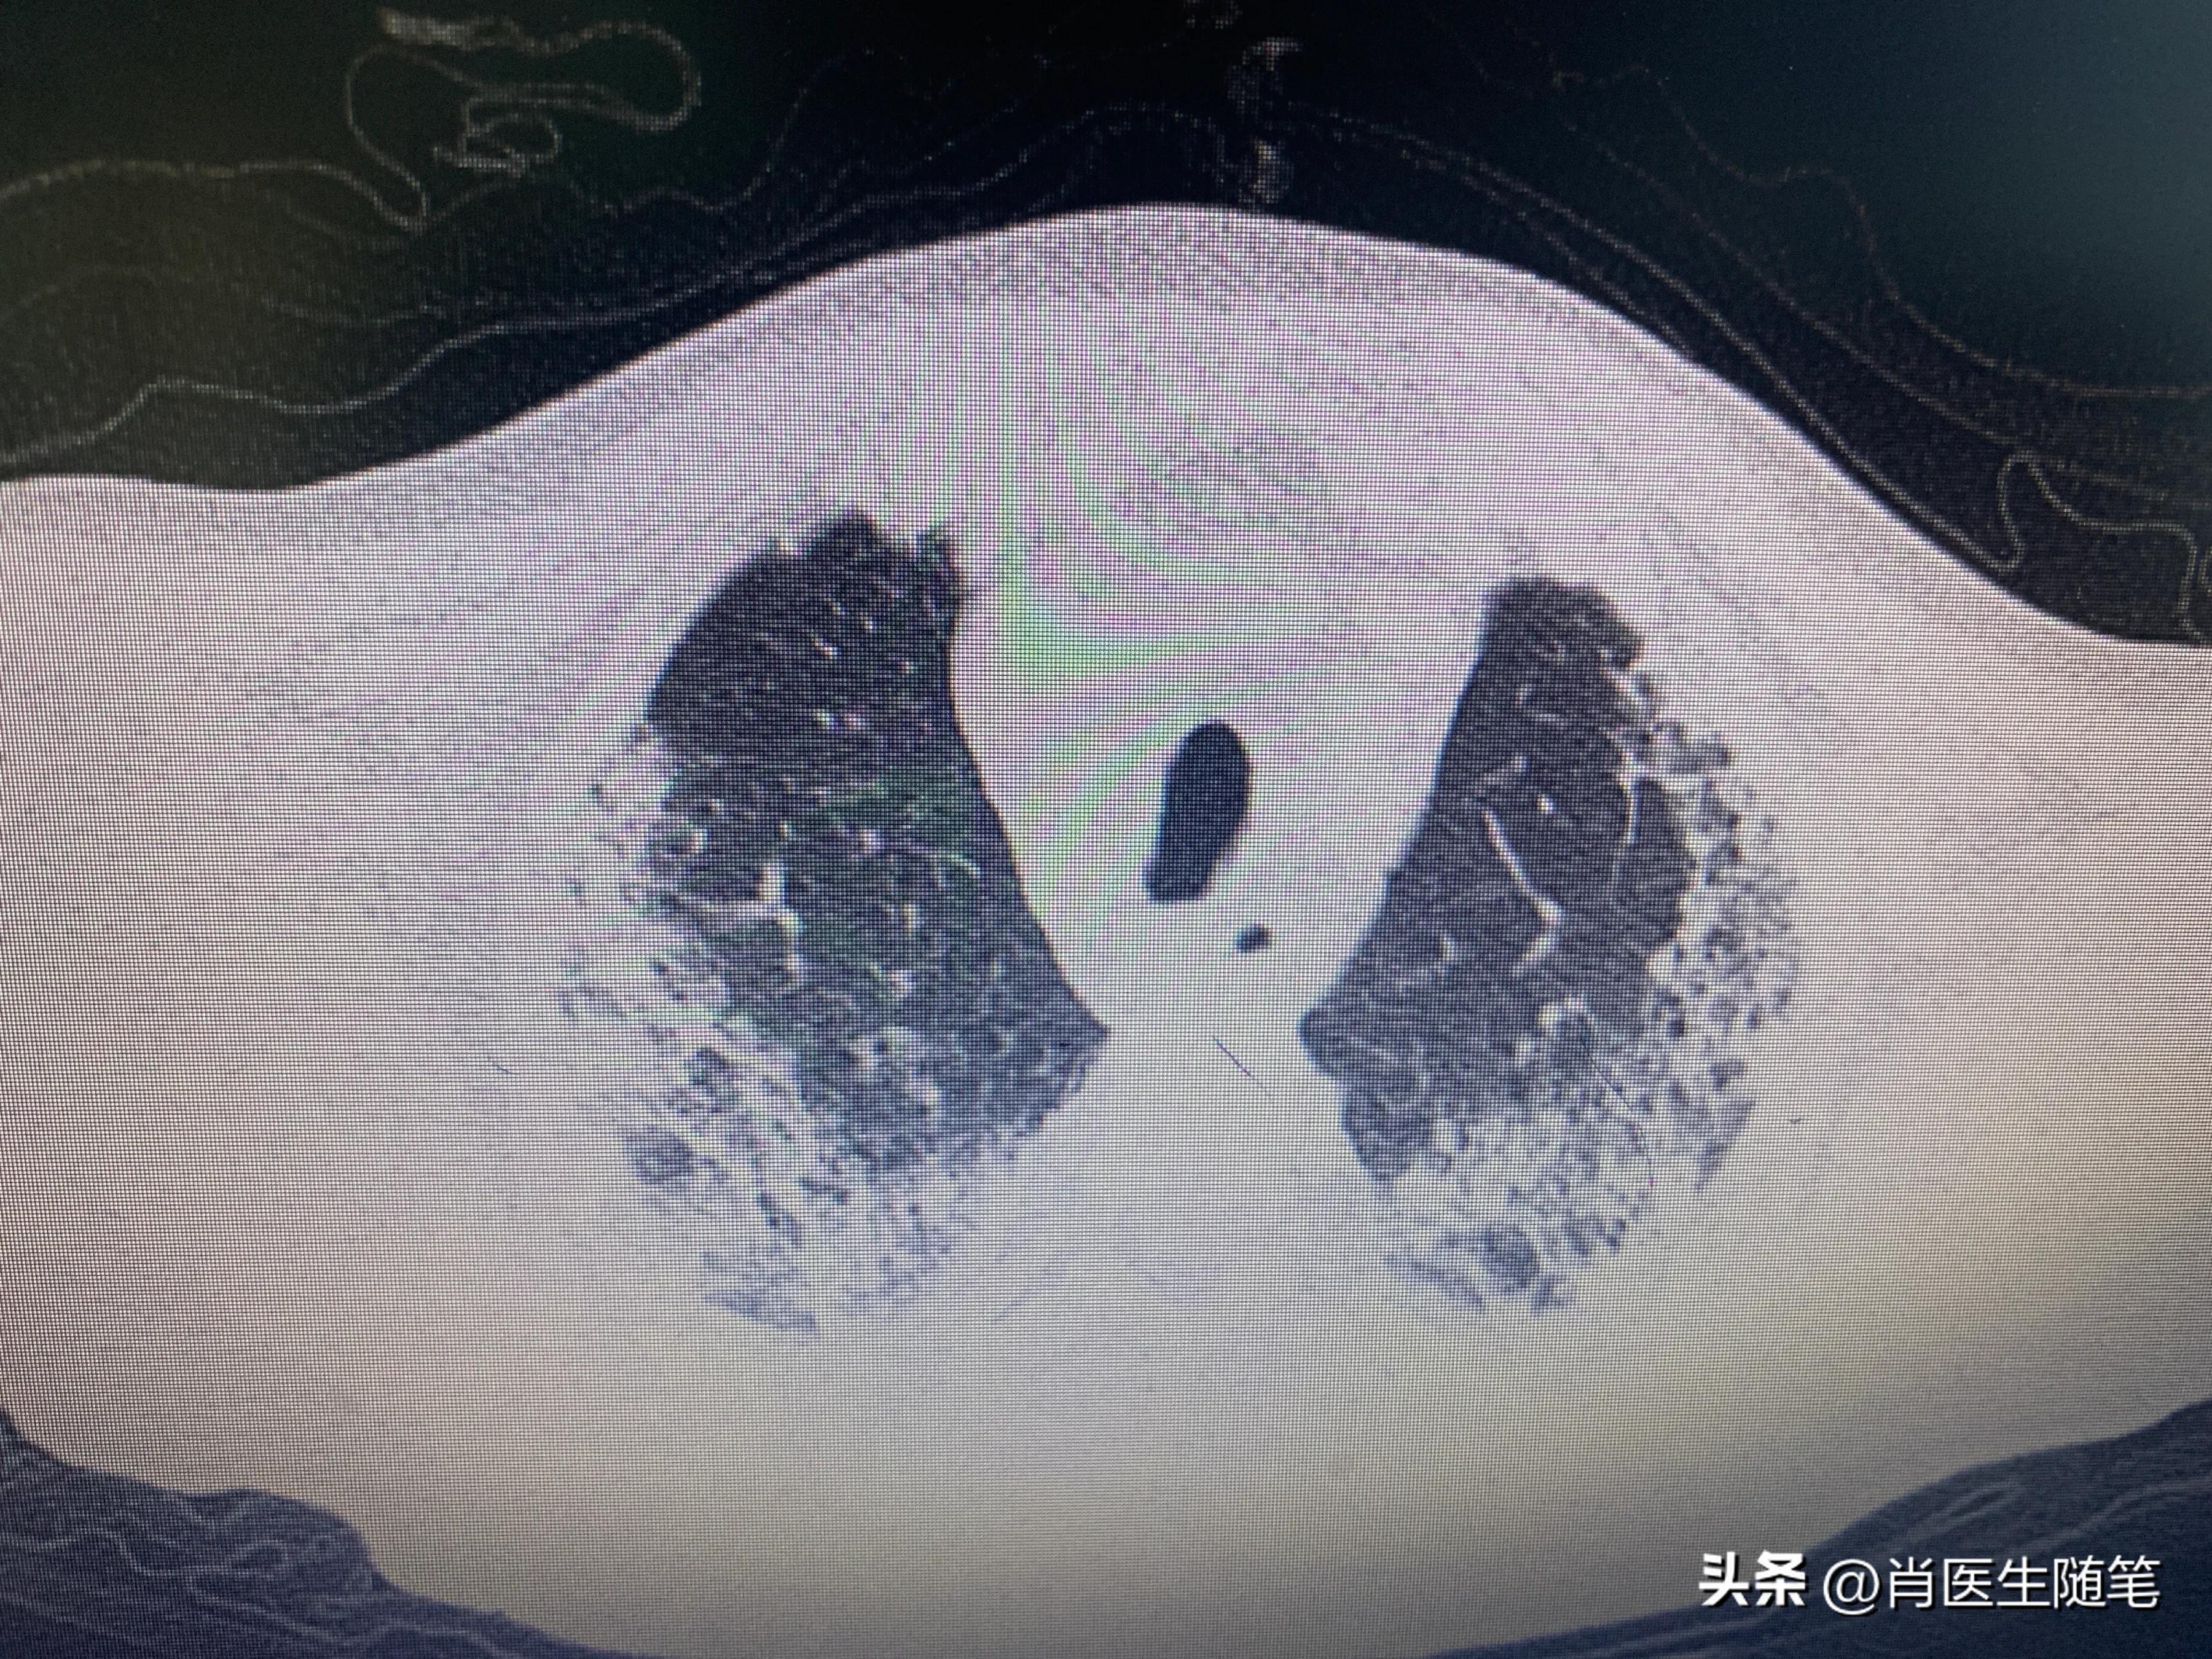

入院后2023-01-13胸部CT提示双肺炎症,纵膈多发淋巴结显示,部分钙化,双侧胸腔积液,心包积液。血提示炎症指标升高,白蛋白略低,33g/l。血氧饱和度吸氧下95%。